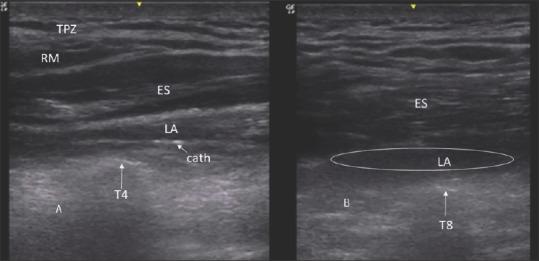

Uncontrolled pain in patients with rib fracture leads to atelectasis and impaired cough which can progress to pneumonia and respiratory failure necessitating mechanical ventilation. Of the various pain modalities, regional anaesthesia (epidural and paravertebral) is better than systemic and oral analgesics. The erector spinae plane block (ESPB) is a new modality in the armamentarium for the management of pain in multiple rib fractures, which is simple to perform and without major complications. We report a case series where ESPB helped in weaning the patients from mechanical ventilation. Further randomised controlled studies are warranted in comparing their efficacy in relation to other regional anaesthetic techniques.

肋骨骨折患者的疼痛若未得到控制,会导致肺不张和咳嗽功能受损,进而可能发展为肺炎和呼吸衰竭,需要进行机械通气。在各种疼痛治疗方式中,区域麻醉(硬膜外麻醉和椎旁麻醉)优于全身和口服镇痛药。竖脊肌平面阻滞(ESPB)是用于治疗多根肋骨骨折疼痛的一种新方法,操作简单且无重大并发症。我们报告了一组病例,其中ESPB有助于患者脱离机械通气。有必要进一步开展随机对照研究,以比较其与其他区域麻醉技术的疗效。